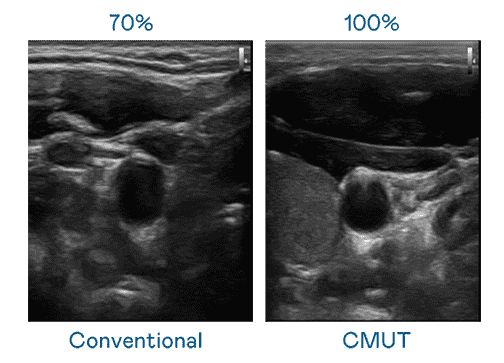

CMUT 技术是一种用电容式微机电元件来产生超音波讯号的技术。。。与传统 PZT 压电式技术相比,,,CMUT 频宽增加 30%,,,,更宽频的超音波讯号让影像解析度大幅提升,,,,是实现高影像品质医疗超音波扫描、、促进精准医疗发展的关键技术。。。

超音波影像的解析度高低,,首先取决于探头能发出的讯号频宽。。EBpay CMUT 可提供高清晰的超音波讯号,,提供高频宽、、、高灵敏度、、、、影像纹理细节更高的超音波影像,,,协助医护人员缩短影像判读时间及利用精准的医疗影像进行诊断。。。